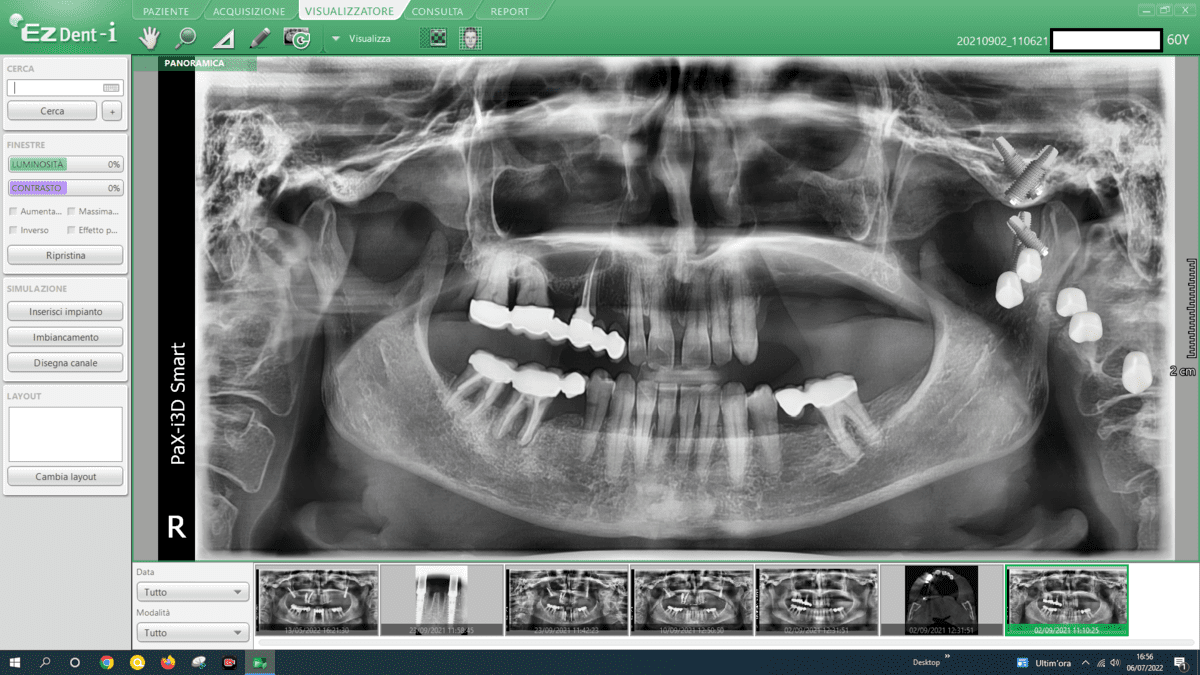

- All-on-4 or All-on-6 Procedures:

- A more comprehensive surgery like Galileus Cerclage Sinus® would be more beneficial. These procedures involve placing a fixed prosthesis supported by four or six dental implants. The strategic placement of implants allows support for an entire arch of teeth, relying less on extensive bone support.

- Advanced Implant Techniques:

- Advanced implant techniques, such as Galileus Cerclage Sinus® mentioned in previous conversations, can offer innovative solutions for addressing atrophies. These techniques focus on strategically placing implants to optimize bone utilization.

- Computer-Assisted Surgery:

- Computer-assisted surgery and digital planning play a significant role in optimizing implant placement, ensuring precision, and minimizing invasiveness in areas with bone atrophy.